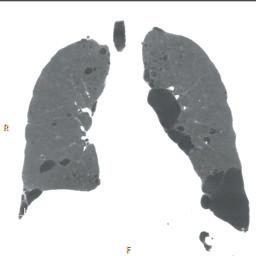

FIGURE 1-15 Coronal minimum intensity projection (MinIP) of a chest CT.

ranges of CT density to each visible shade of gray but is perceived as a very low contrast, or very gray, image (Fig. 1-20).